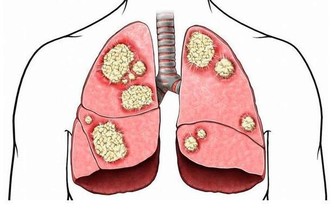

第一個就是體內的褪黑素正在逐漸降低分泌

如果說晚上睡眠不是很好,大多都是因為體內的褪黑素正在不斷的減少,這是我們身體分泌出來的一種物質,如果體內缺少了這種物質,那麼就會出現睡不著的現象。尤其是年齡逐漸的增加,這種物質分泌太少就會出現睡眠問題,這也是很多老年人會出現睡不著現象的主要原因。